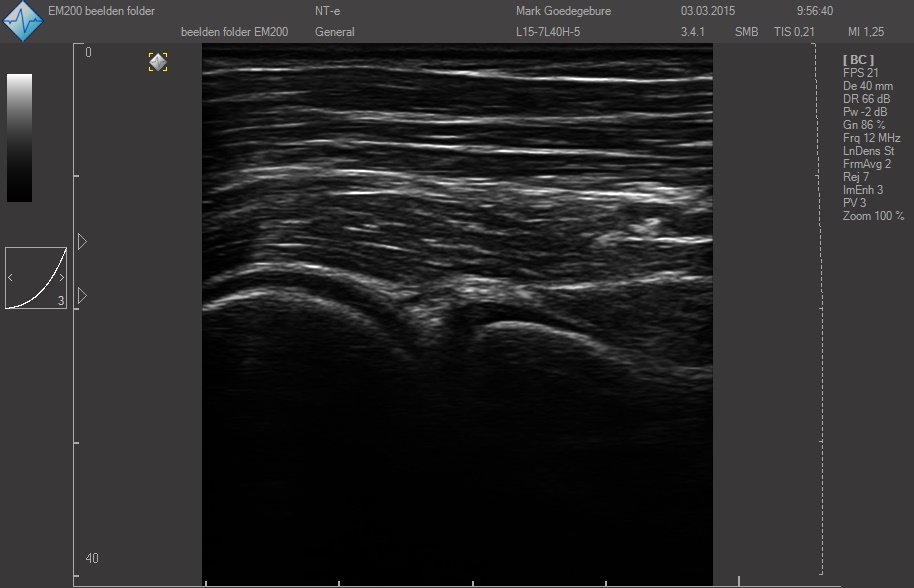

Датчики имеют большую чувствительность и высокое разрешение, благодаря чему обеспечивают максимальное проникновение и улучшают соотношение сигнал /шум. В результате формируется максимально четкая детализированная картинка УЗИ изображения.

ЗДЕСЬ Вы можете посмотреть реальные кинопетли с аппарата УЗИ SmartUs.